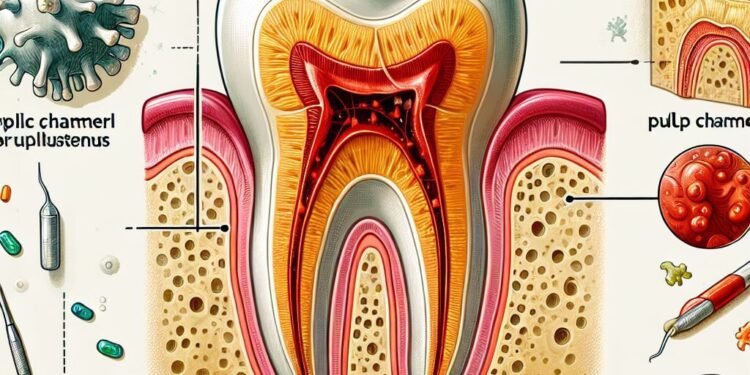

A pulpite reversível é uma condição odontológica que afeta a polpa dental, a parte interna do dente composta por nervos e vasos sanguíneos. Trata-se de uma inflamação inicial da polpa que, se identificada e tratada corretamente, pode ser revertida sem a necessidade de procedimentos invasivos, como a endodontia (tratamento de canal). Compreender os sinais, causas, diagnóstico e tratamentos da pulpite reversível é essencial para preservar a saúde dental e evitar complicações mais graves.

A pulpite reversível corresponde a uma inflamação superficial da polpa dentária, geralmente provocada por estímulos agudos, mas que ainda não comprometeram de forma irreversível a vitalidade pulpar. Nessa fase, a polpa pode se regenerar e retornar ao estado saudável, caso o agente causador seja eliminado e o dente receba o tratamento adequado.

É importante destacar que a pulpite reversível difere da pulpite irreversível, na qual a inflamação é profunda e persistente, levando à necrose da polpa e à necessidade de tratamento endodôntico para resolver o problema.

A pulpite reversível ocorre quando a polpa dentária sofre um estímulo nocivo, mas sem dano severo. Entre as principais causas estão:

- Cáries dentárias iniciais: A invasão da cárie até próximo à polpa pode provocar irritação;

- Desgaste dentário: O atrito excessivo ou abrasão pode expor dentina e causar inflamação;

- Procedimentos odontológicos: Preparações cavitárias ou restaurações mal adaptadas podem gerar irritação temporária;

- Trauma dentário: Impactos ou forças excessivas podem causar inflamação pulpar;

- Bruxismo: O hábito de ranger os dentes com força pode levar à irritação pulpar;

- Exposição dentinária: Recessões gengivais e erosão podem deixar a dentina exposta, facilitando o acesso de irritantes.